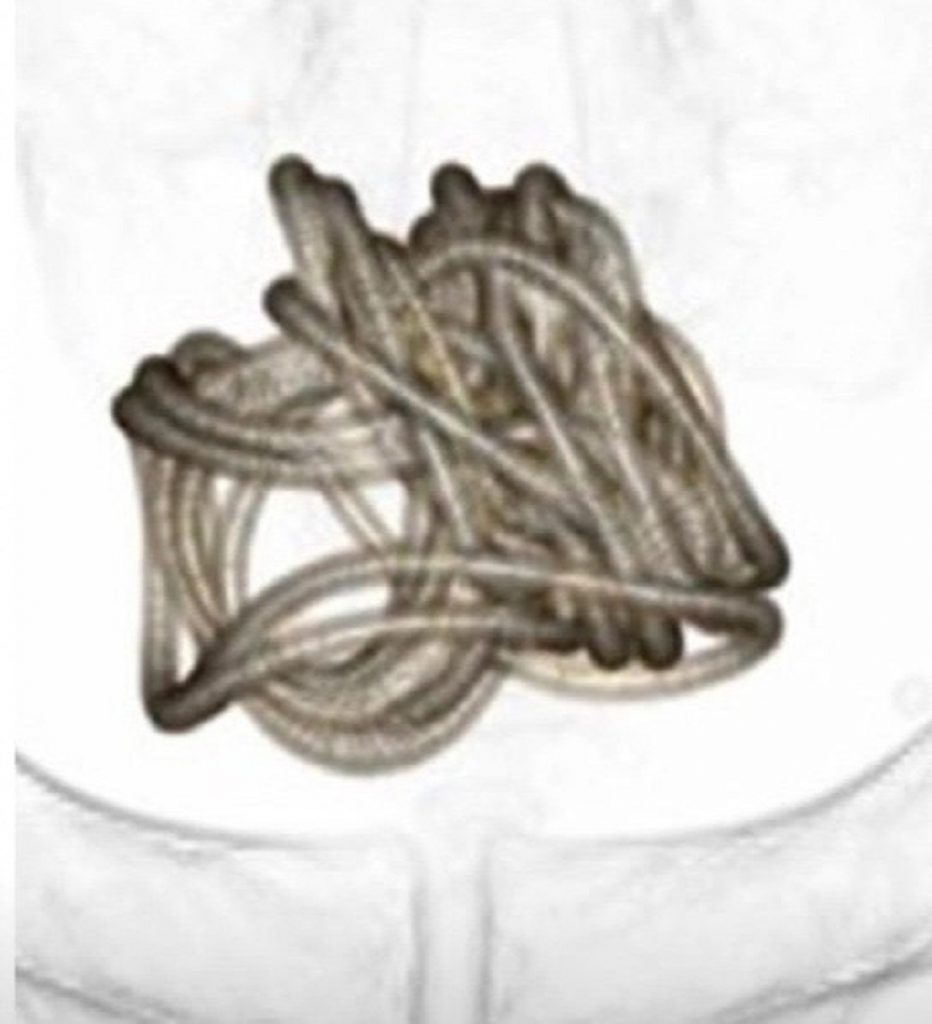

Les scans publiés par ses médecins montrent la corde étroitement enroulée à l’intérieur de la vessie de l’homme non identifié. Les médecins ont dû couper la vessie de l’homme pour l’extraire chirurgicalement et ils n’ont pas pu la retirer comme elle est entrée.

Les médecins ont utilisé des informations provenant d’analyses détaillées pour créer un modèle informatique 3D de la corde emmêlée afin de déterminer la meilleure méthode de retrait. L’homme n’a pas dit aux médecins pourquoi il avait inséré la corde.

Des experts de l’Université médicale de Dokkyo dans la ville de Mibu, à 100 km au nord de Tokyo, ont détaillé l’incident dans un rapport de cas médical. L’homme s’est rendu au centre médical de l’université pour se plaindre de dysurie, une sensation douloureuse ou brûlante au moment d’uriner. Lorsque les médecins ont examiné sa vessie à l’aide d’un scanner à ultrasons, ils ont découvert qu' »un gros objet accompagné d’ombres acoustiques » se trouvait à l’intérieur de la vessie. Une radiographie a ensuite révélé que cet objet était « un corps étranger enroulé en forme de fil ». L’homme a ensuite été contraint d’admettre aux médecins qu’il avait inséré une corde à sauter dans l’urètre du p3nis.

L’auteur principal du rapport de cas, publié dans la revue Urology Case Reports, l’urologue professeur Toshiki Kijima, a déclaré que les médecins avaient ensuite effectué un scanner pour déterminer la meilleure façon de retirer la corde. Il a dit qu’ils avaient ensuite utilisé un programme informatique pour générer une reconstruction 3D de la corde qui montrait qu’elle était devenue trop enchevêtrée pour la retirer à travers le p3nis. La corde s’est emmêlée lorsque la vessie s’est contractée, un processus naturel qui se produit après l’expulsion de l’urine stockée. « L’extraction transurétrale était difficile compte tenu de la longueur de la corde et de son enchevêtrement dans la vessie », a déclaré le professeur Kijima.